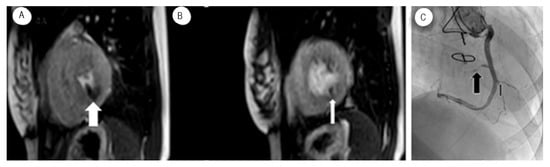

Adenosine Stress Perfusion Cardiac Magnetic Resonance Imaging

Myocardial perfusion reserve measured by CMR is valuable and accurate in diagnosing adult CAV [57]. Myocardial perfusion reserve is the ratio of the myocardial blood flow during hyperemia to the myocardial blood flow at rest. Few studies showed that adenosine perfusion CMR imaging could be performed safely even in higher grade CAV in pediatric HT recipients [58]. Figure 5 illustrates an adenosine perfusion study in a 17-year-old HT recipient showing inferior ischemia and perfusion defect that correlates to CAV in the coronary angiogram.

Figure 5. (A,B) MRI Perfusion images showing inferior ischemia induced by Adenosine (white arrow) in a patient with known CAV (C) Black arrows showing stenosis on selective coronary angiogram.